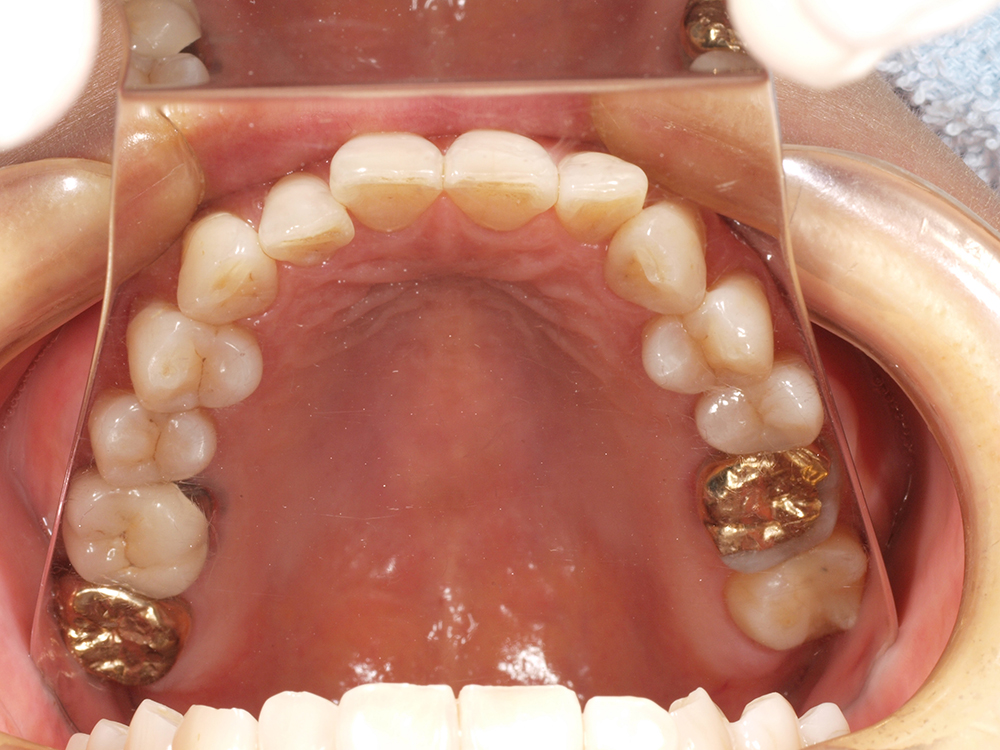

55歳 男性

- 主訴

- 前歯でしか咬めなく、食事を採るのに非常に困難で辛い

- 処置内容

- 上顎6本、下顎3本

- 治療費用

- 上顎:約230万(税込)下顎:約120万(税込)

- 治療期間

- 上顎:1年(仮歯まで8か月)下顎:8か月(仮歯まで5か月)

- リスク

- 上部構造物、仮歯の破折、術後の腫れ(3日)、人工歯根脱落リスクがあります